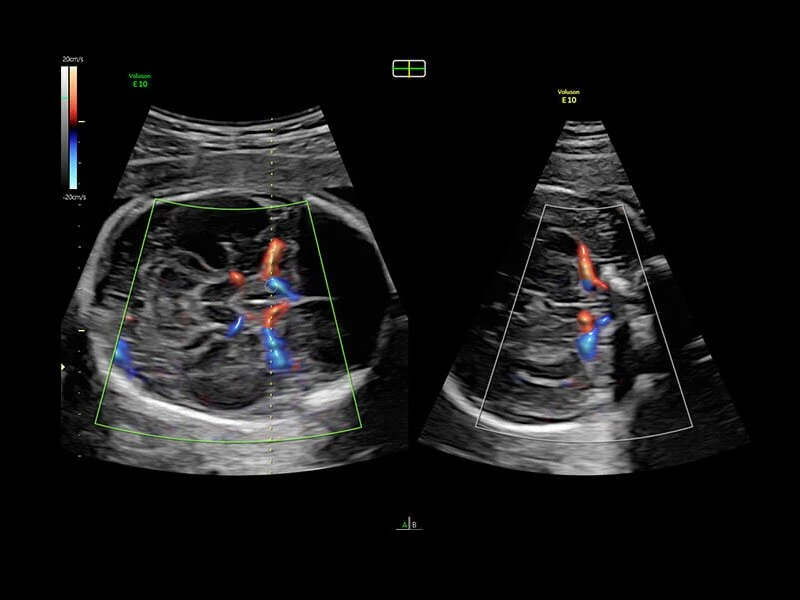

Voluson E10 – премиум класс среди ультразвуковых диагностических аппаратов для акушерских, гинекологических и объемных исследований. Аналогов системе Voluson E10 на рынке не представлено. УЗИ аппарат Voluson E10 обладает возможностью подключения электронного матричного датчика с количеством элементов не менее 8000.

Ультразвуковой аппарат идеально подходит для акушерско- гинекологических исследований. Гарантирует точное и четкое изображение.

Система обеспечивает инновационную четкость при работе. Новая платформа Radiance System Architecture системы разработана для превосходной визуализации как в стандартных режимах, так и при 3D/4D-визуализации.

Она оснащена инструментами, которые упрощают получение изображений, отличается высокой чувствительностью цветового допплера, поддерживает инновационные 3D/4D технологии.

Объемное УЗИ на Voluson E10 — это не просто потрясающе красивая картинка, это ценный инструмент получения дополнительной информации при обследовании женщин.

Voluson E10 поддерживает инновационные технологии формирования изображений — HDlive Silhouette и HDlive Flow, которые позволяют увидеть мельчайшие детали. Алгоритм SonoRenderlive упрощает рабочий процесс и дает возможность реконструировать изображение поверхностей, определяя область перехода между тканью и жидкостью.

- Технология HDlive Flow — повышает реалистичность визуализации сосудистых структур, улучшая восприятие глубины (по сравнению с традиционным цветовым допплером и функцией HD-Flow).